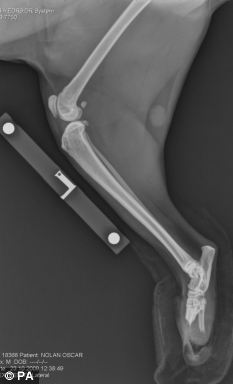

奥斯卡接受义肢安装手术前后腿的骨骼透视照片

菲茨帕特里克医生利用英国伦敦大学开发的骨内义肢技术,把钛等金属材料制成的义肢伸入奥斯卡的后腿皮肤内与它的断肢处骨骼相连,另一端留在皮肤外以便安装机械猫爪,猫爪可在一定范围内活动,让奥斯卡能够像其它猫一样走路、跑跳甚至攀爬到高处。